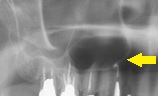

鼻腔と口腔は上顎によって隔たれているのですが、上の奥歯には

上顎洞という副鼻腔に分類される空洞があります。

これは臼歯部と眼の間にある空洞なのですが、これが加齢によって

上顎洞が大きくなっていくことがあります。

これを含気化(Pneumatization)と呼びます。

上顎洞が大きくなっていくと結果的には上顎の骨(歯槽骨)が

薄くなっていきますので、いざインプラントをしたい、となった場合に

骨が足りないということも起こっていくることになります。